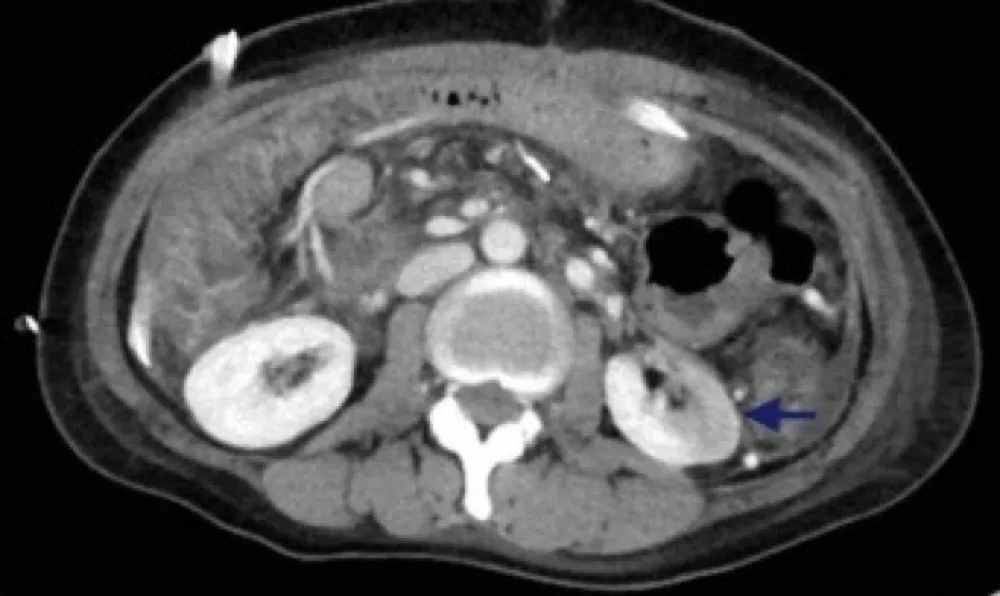

Uma causa incomum de hematúria glomerular intermitente!

Uma causa incomum de hematúria glomerular intermitente!

Hematúria pós infecção, caso clínicos para auxiliar no entendimento de causas glomerulares comuns e raras...